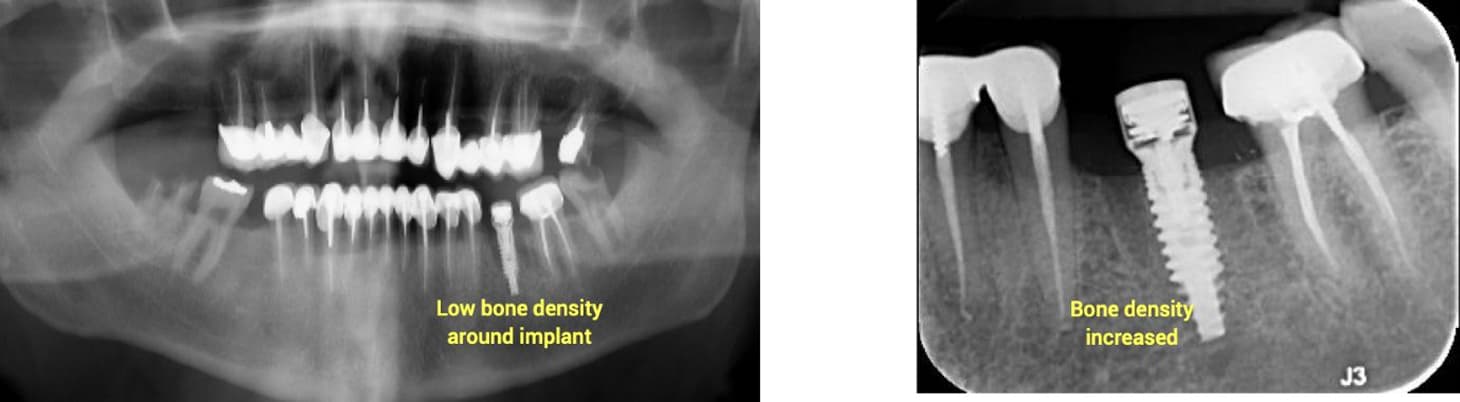

Case Summary: A 35-year-old female presented with a red, edematous bulge (2.5 mm diameter) two months after implant placement in site #45, previously extracted due to vertical root fracture. A periapical X-ray revealed early signs of bone loss at the coronal level, indicating inflammatory environment onset.

Treatment Approach: A Magdent MED healing abutment was placed for 60 days to deliver localized PEMF therapy and promote tissue regeneration around the implant.

Clinical Outcome:

• Inflammation and edema fully resolved

• Bone density and level significantly improved (confirmed via X-ray)

• Implant clinically stable and asymptomatic